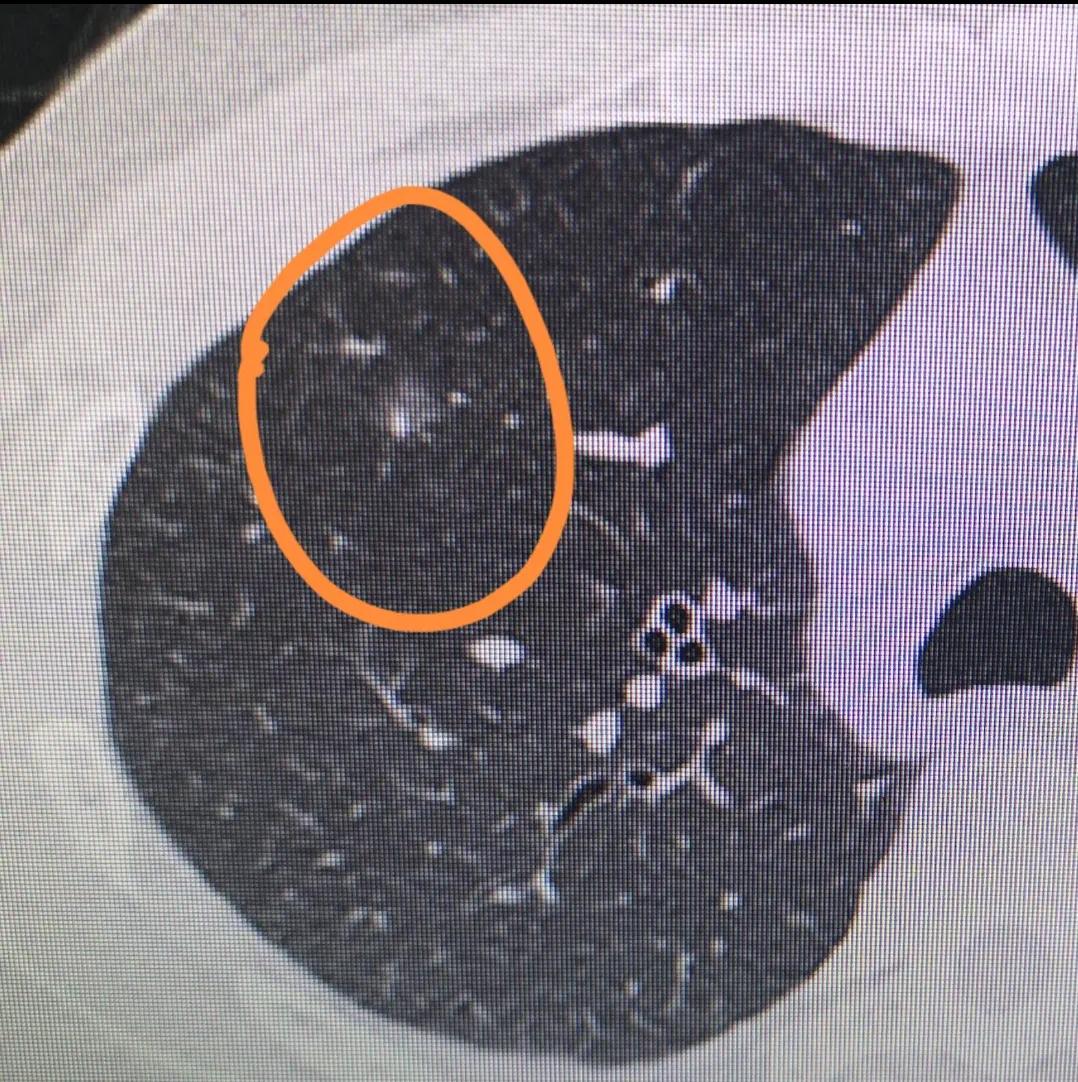

观察肺结节的变化可以通过定期进行胸部CT扫描或X射线检查来实现。这些检查可以帮助医生了解结节的大小、形态和变化情况。如果结节在短时间内有显著增大或出现其他异常改变,可能需要进一步进行检查,例如PET-CT扫描或活检等。

需要注意的是,肺结节的类型需要通过影像学检查(如CT扫描)来确定,但仅通过CT影像无法确定结节的性质,还需要结合其他临床信息以及必要的生物组织学检查(如活检)来做出最终的诊断。